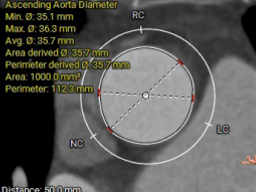

STJ周长:88.6mm

升主动脉周长:112.3mm

法氏窦

右冠状窦直径:28.8mm;左冠状窦直径:30.8mm;无冠状窦直径:32.5mm